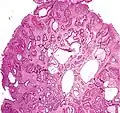

Juvenile Polyp Upper GI tract and colon Cystically dilated glands with expanded lamina propria Not inherently, may develop dysplasia

Juvenile polyposis syndrome, identical polyps in Cronkhite–Canada syndrome